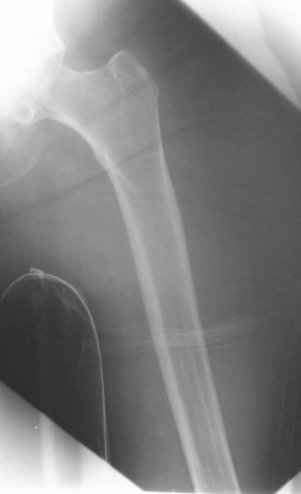

My preference would be to rigidly fix the fracture internally. I just feel that it may not be possible given the very porotic nature of the bone distal to the fracture (I am re-sending the lateral x-ray which really concerns me).

I doubt if I could lock a nail (either antegrade or retrograde) distal to the fracture which extends virtually to the implant. I have similar concerns about plate fixation. Has anyone got a reasonable volume of experience with this type of fracture?